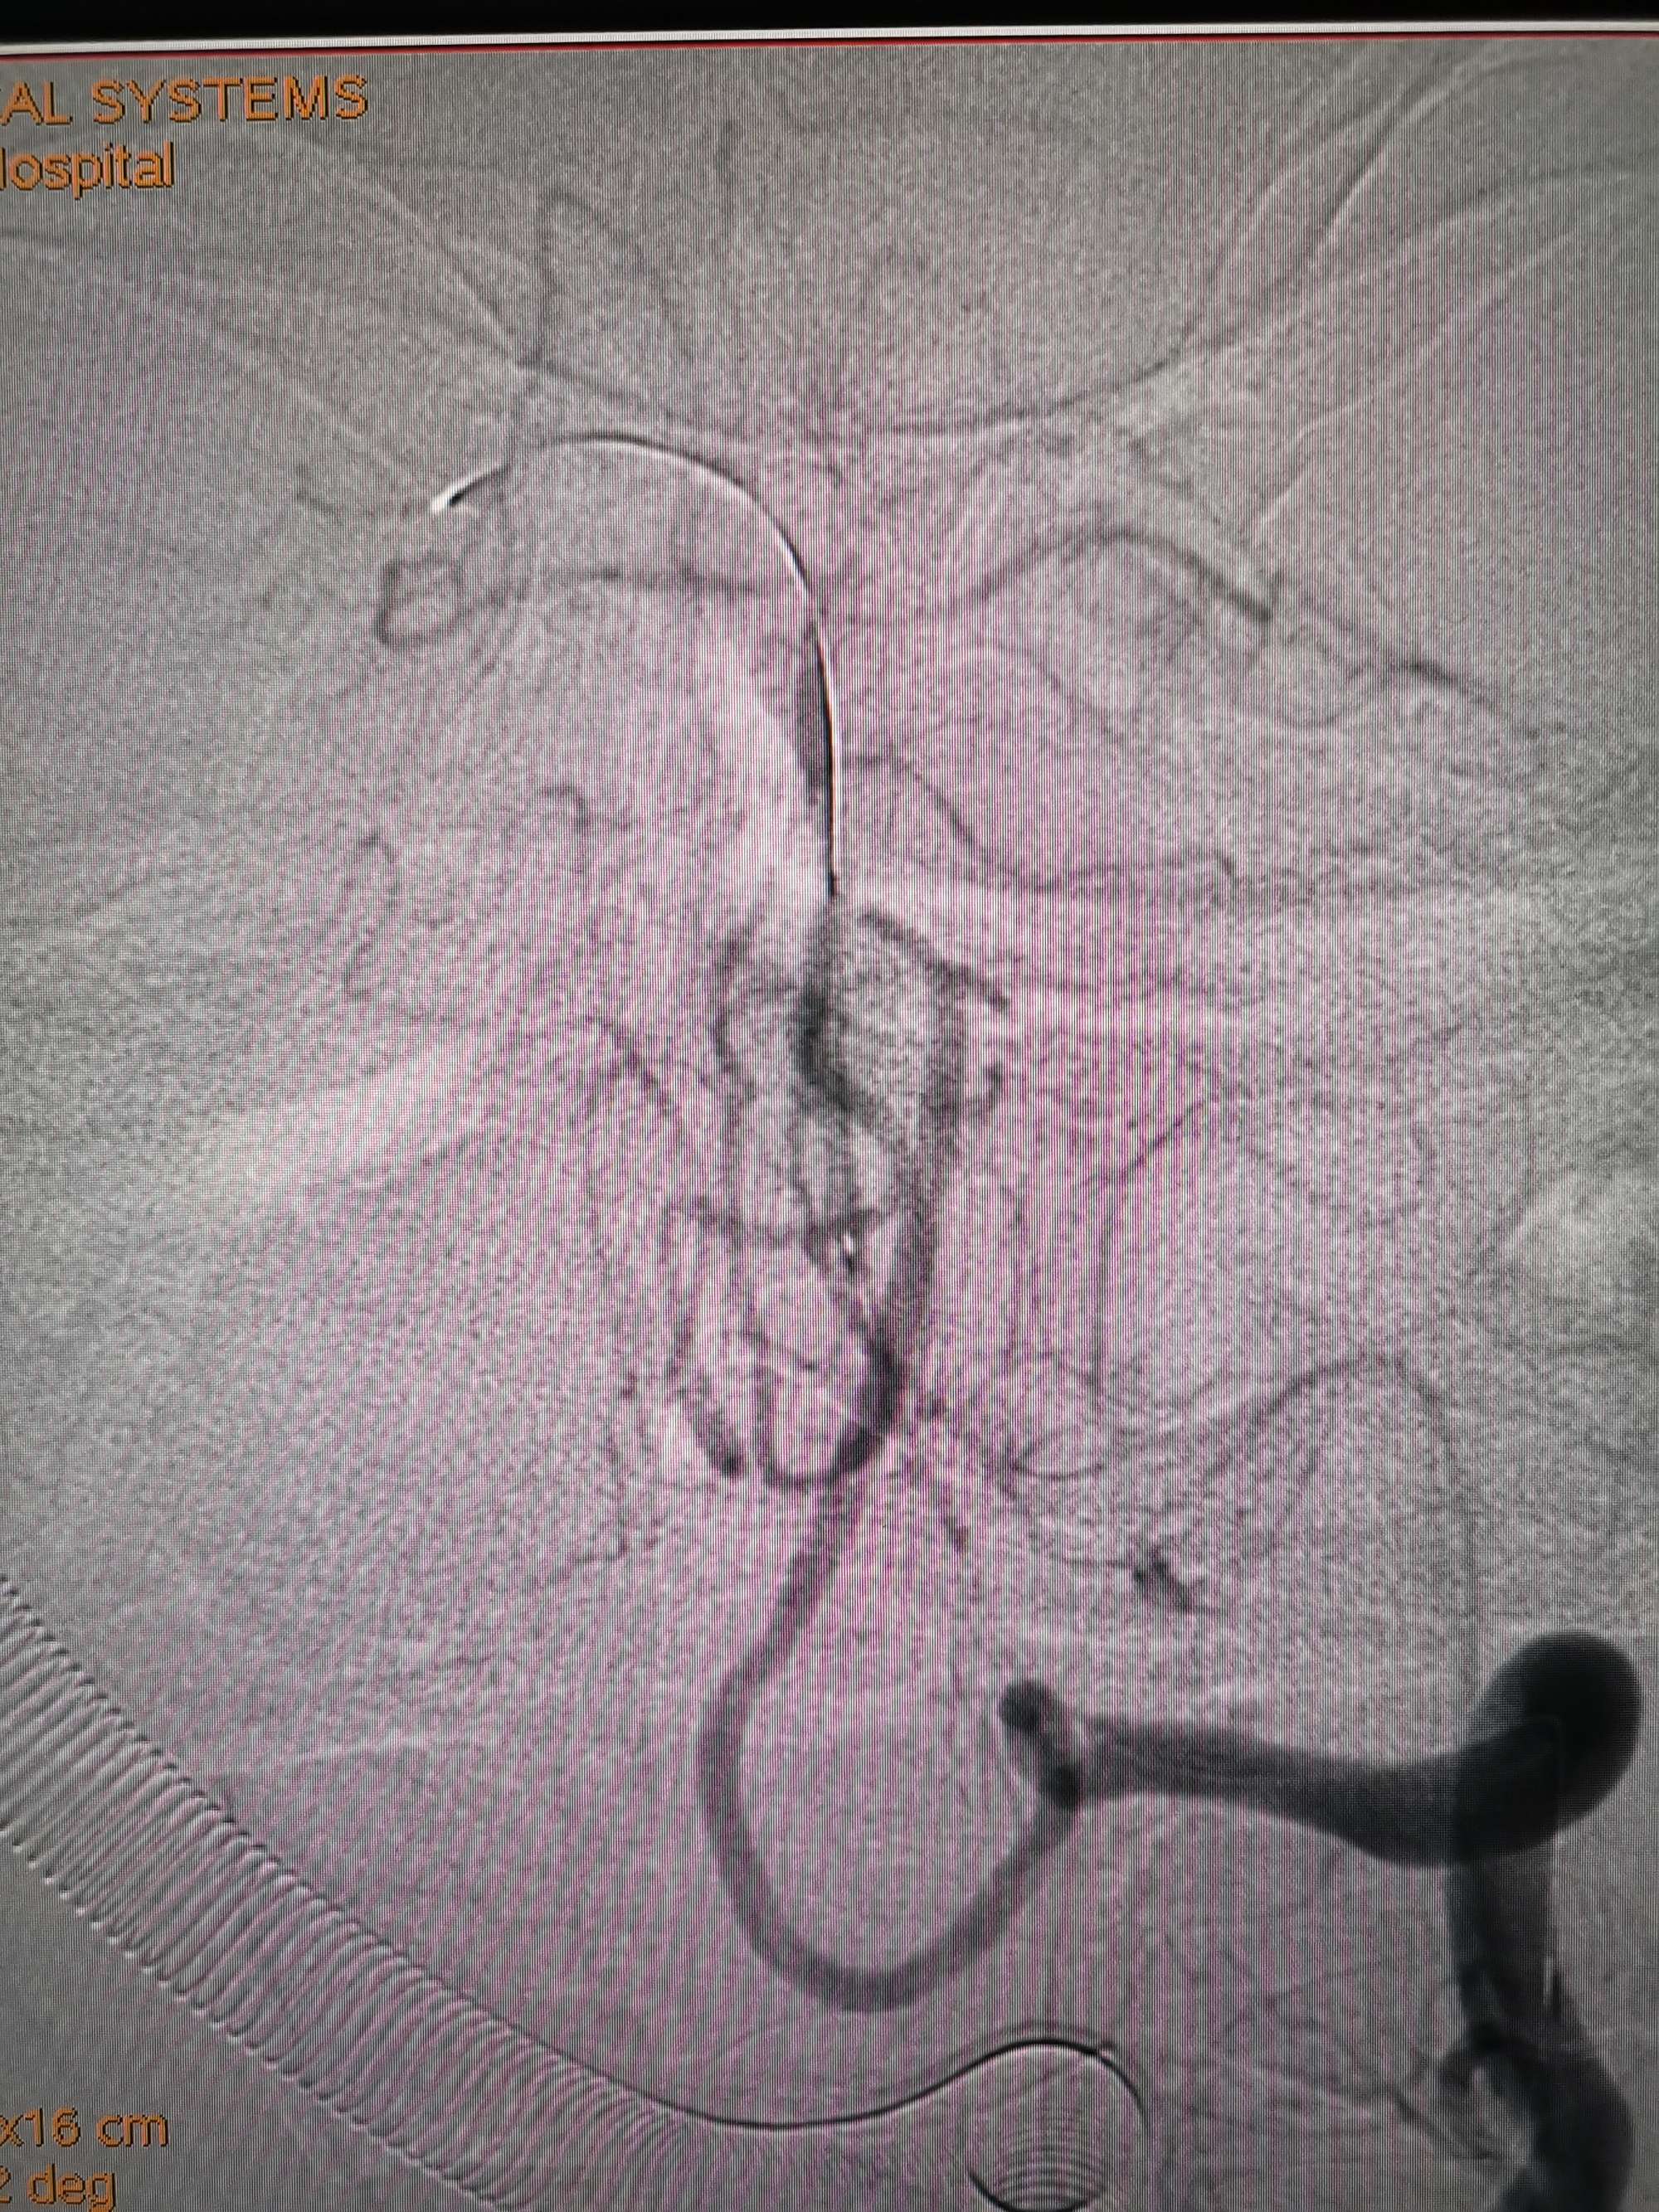

术前再次造影评估

右侧椎动脉穿支供血及左侧PICA供血较入院时略有改善,但改善不明显。故按计划行左侧椎动脉再通术